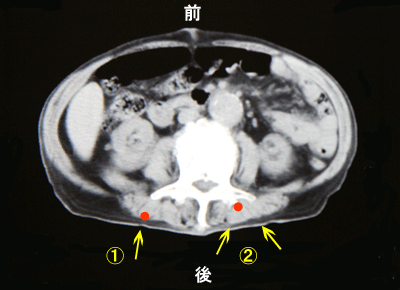

体幹のCT像  腰椎を含む断面

右図の@赤い点のように浅い部分に痛

みの中心があれば、矢印のように比較的

正確に痛む部分を指し示すことができま

す。ところが、Aのように深い部分に痛み

の中心がある場合には、体表の一部を指

し示すだけでは正確な部位がわかりませ

ん。